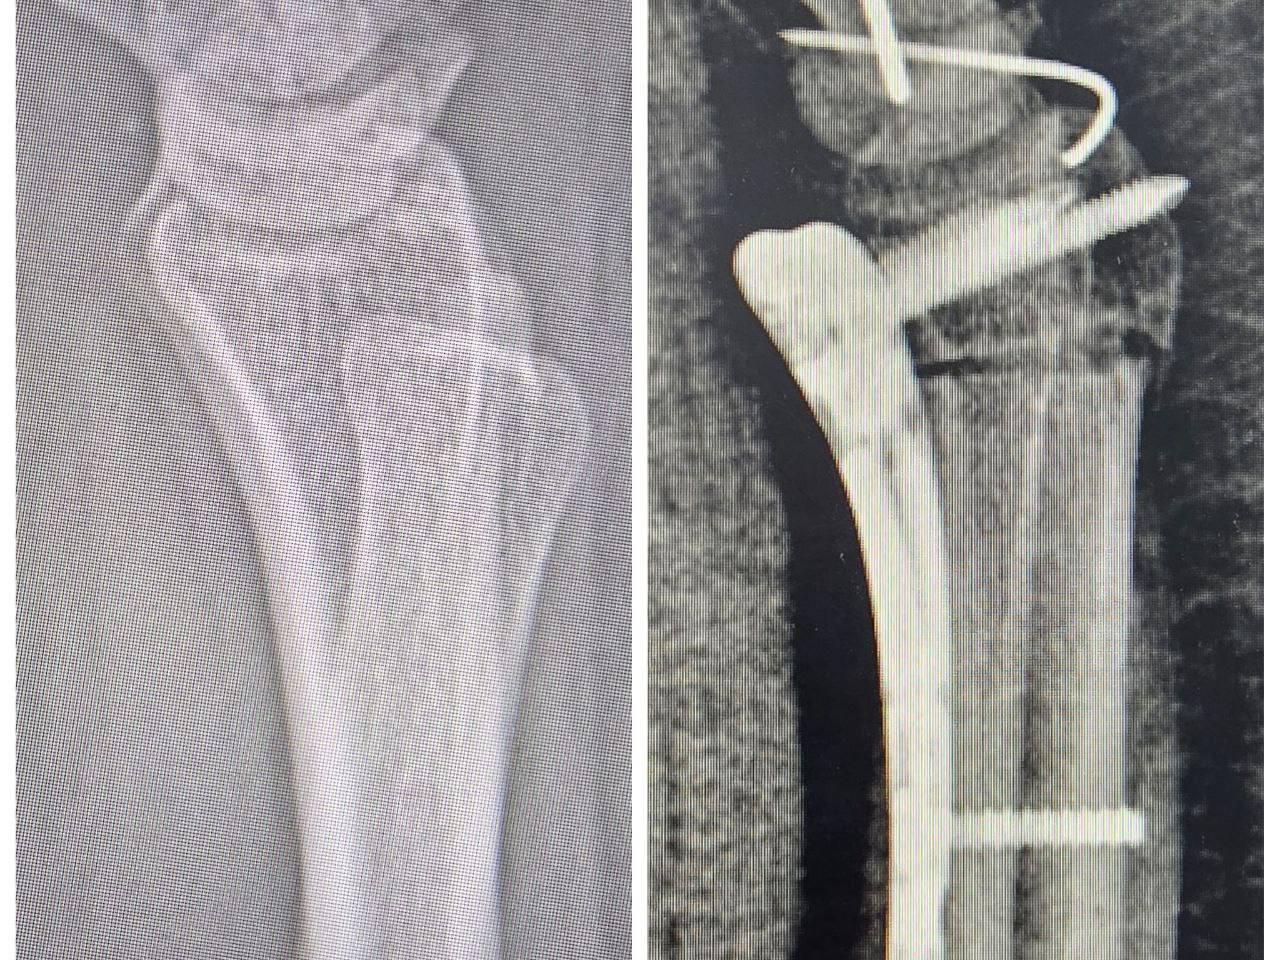

Transplanted a Destroyed Bone

A 24-year-old Tyumen woman had pain in her wrist for about a year. Doctors examined her and discovered a very rare pathology — Kienböck«s disease. Because of it, the blood supply to the hand is disrupted and the lunate bone dies. Surgeons had to transplant bone for the patient and restore mobility to the hand.

First, specialists at the Center for Reconstructive Hand Microsurgery performed an osteotomy to reduce pressure on the damaged bone.

Osteotomy is a surgical operation involving artificial cutting of a bone to correct its shape, position, or length.

After that, the doctors took a fragment of the iliac bone from the young woman, preserving its blood vessels. They were immediately sutured to the vessels of the wrist to nourish the lunate bone. The operation was successful. After six weeks of rest, the patient began rehabilitation.